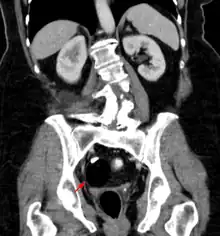

The most diagnosed fetal teratomas are sacrococcygeal teratoma (Altman types I, II, and III) and cervical (neck) teratoma. Because these teratomas project from the fetal body into the surrounding amniotic fluid, they can be seen during routine prenatal ultrasound exams. Teratomas within the fetal body are less easily seen with ultrasound; for these, MRI of the pregnant uterus is more informative.[26][27]

Diagnosis

Teratomas are thought to originate in utero, so can be considered congenital tumors. Many teratomas are not diagnosed until much later in childhood or in adulthood. Large tumors are more likely to be diagnosed early on. Sacrococcygeal and cervical teratomas are often detected by prenatal ultrasound. Additional diagnostic methods may include prenatal magnetic resonance imaging. In rare circumstances, the tumor is so large that the fetus may be damaged or die. In the case of large sacrococcygeal teratomas, a significant portion of the fetus' blood flow is redirected toward the teratoma (a phenomenon called steal syndrome), causing heart failure, or hydrops, of the fetus. In certain cases, fetal surgery may be indicated.

Beyond the newborn period, symptoms of a teratoma depend on its location and organ of origin. Ovarian teratomas often present with abdominal or pelvic pain, caused by torsion of the ovary or irritation of its ligaments. A recently discovered condition where ovarian teratomas cause encephalitis associated with antibodies against the N-methyl-D-aspartate receptor antibody (NMDAR) - often referred to as "anti-NMDA receptor encephalitis", was identified as a serious complication. Patients develop a multistage illness that progresses from psychosis, memory deficits, seizures, and language disintegration into a state of unresponsiveness with catatonic features often associated with abnormal movements, and autonomic and breathing instability.[34] Testicular teratomas present as a palpable mass in the testis; mediastinal teratomas often cause compression of the lungs or the airways and may present with chest pain and/or respiratory symptoms.